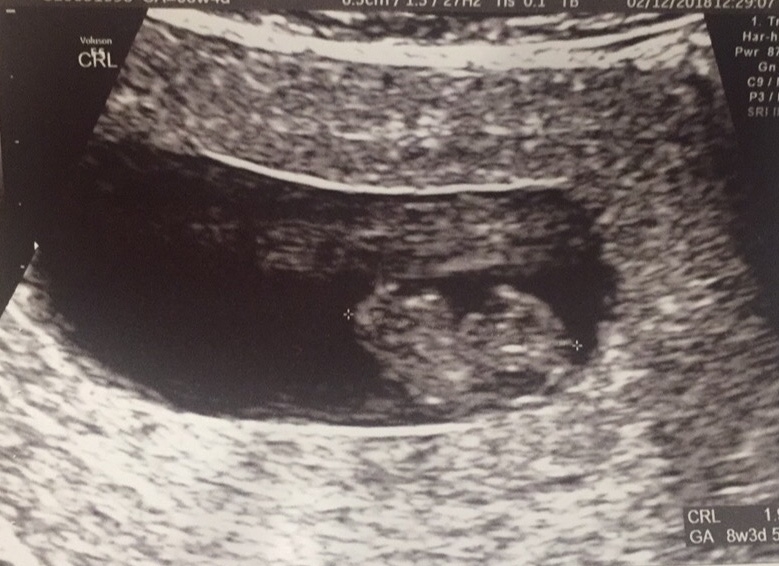

• This is my ultrasound at 8 weeks and 3days 165bpm and 1.9cm(which i hear is big?)